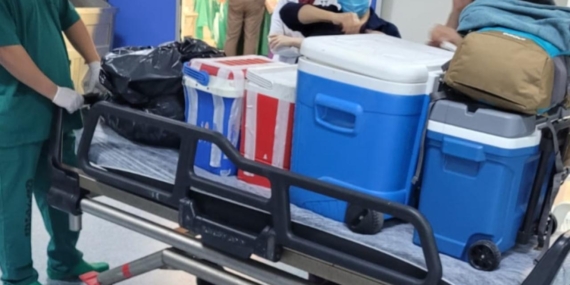

Tedavide Erken Müdahale Hayati Önem Taşıyor

Zatürre tedavisinde amaç; enfeksiyonu ortadan kaldırmak, akciğer fonksiyonlarını yeniden düzenlemek ve nefes darlığı ya da organ yetmezliği gibi komplikasyonları önlemek.